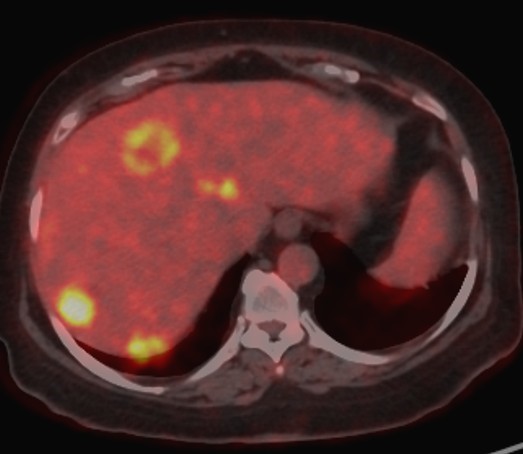

Figure 2a. A case of a 58-year-old male patient with colorectal cancer liver metastases. Axial fused 18F-FDG PET-CT image showing multiple FDG-avid hepatic metastases with increased metabolic activity.